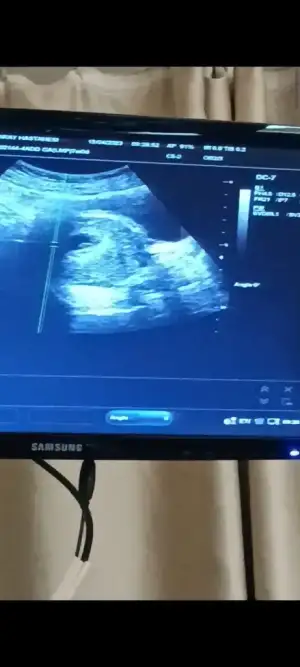

şaşkınlığımdan ultrason fotoğrafını yolda düşürmüşüm bulamadık ama videodan ekran görüntüsü aldım bi yorumlarsanız çok sevinirim

doktor kanama alanı yok kese çok güzel kalbi de iyi atıyor hiç bir sorun yok lekelneme de rahimden kaynaklı değil dedi fitili değiştirdi ağızdan alınan başka bir progestan verdi 11. Haftada gel dedi içim Cook rahtladi inşallah sağlıklı bir şekilde de ilerler

(karından ultrason)